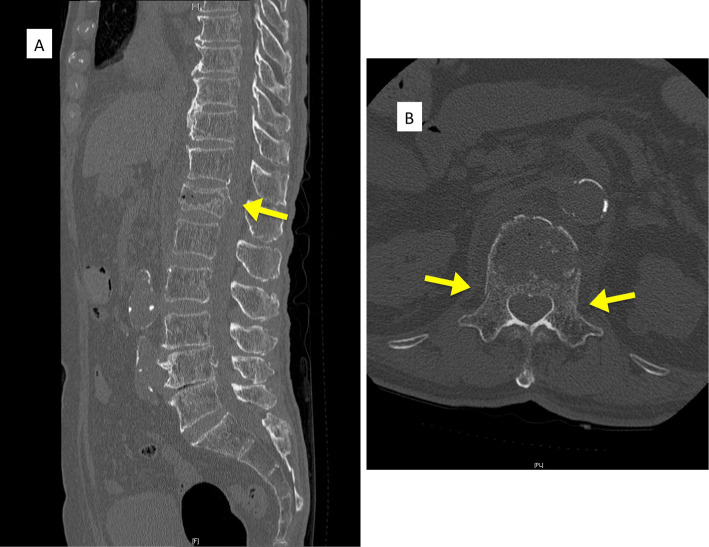

Methods: Surgical indications are a vertebral wedge angle difference of 10° or more, vertebral pedicle fractures, posterior wall fractures, and diffuse low-signal changes exceeding 50% on T1-weighted magnetic resonance imaging. The procedure is reserved for highly unstable cases following a comprehensive health assessment. The surgical technique involves prone positioning, fluoroscopy-guided percutaneous vertebral augmentation, and the use of downward PES in the cranial vertebral body and upward PES for the caudal vertebral body by percutaneous technique. The fixation range is one above and one below.

Abstract Image